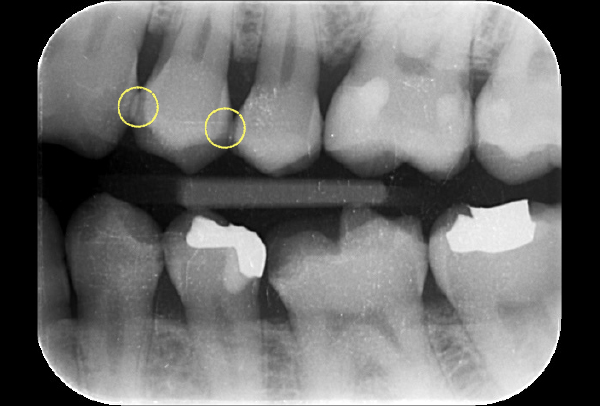

インレー症例

初診時パノラマ

初診時口腔内写真

iTero NIRI機能による診査

虫歯除去後

初診時バイトウィングデンタル

レントゲンだとちょっと虫歯が怪しいくらいに写っている。これだけだと確定診断としては、判断材料が少ないと考えられる。

黄色丸の部位が、他の部位と違って白く抜けがあるのがわかります。これがNIRI機能による虫歯の診査です。

この機能のおかげで、歯と歯の間の見つけにくい虫歯がよくわかるようになってきました。

In(インレー)セット後

年齢・性別 40代・男性

主訴 左上の奥歯がしみることがある

治療内容 左上4の虫歯

治療期間 2週間

リスク・副作用 虫歯の大きさによっては、神経をとらないといけなくなることがあります。

また、虫歯が大きかったケースで神経を残した場合、治療後にしみるなどの

症状が続くことがあります。

費用 ・ジルコニアインレーで修復

55,000円

治療方針

IOSのNIRI機能によって虫歯部分が明らかになったので、虫歯を除去後に修復治療を行うこととしました。

担当医師所見

虫歯の有無を確認する上で今まではレントゲンと自分の目での確認でした。現在は目で見るよりもはるかにわかりやすいIOSという装置がありますので、虫歯の発見がしやすくなりました。

そのため、患者さんの虫歯の進行の段階が早いうちにわかる様になり、神経をとらなければならないというケースが非常に少なくなっています。